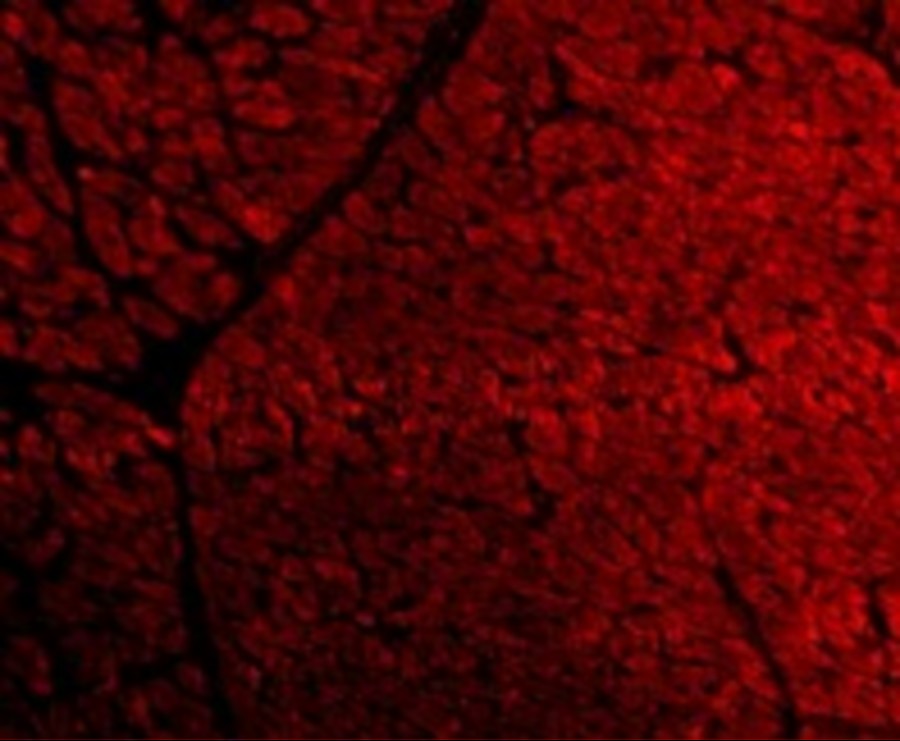

Product information "Anti-TIRAP"

Protein function: Adapter involved in the TLR2 and TLR4 signaling pathways in the innate immune response. Acts via IRAK2 and TRAF-6, leading to the activation of NF-kappa-B, MAPK1, MAPK3 and JNK, and resulting in cytokine secretion and the inflammatory response. Positively regulates the production of TNF-alpha and interleukin-6. [The UniProt Consortium]

| Application: | IHC (paraffin), WB |

| Immunogen: | Synthetic peptide around 15 aa (C-terminus) of Mouse TIRAP |